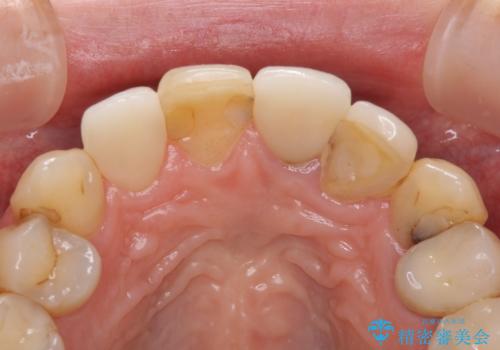

歯肉移植を用いた前歯のオールセラミックブリッジ

- 前歯が折れてしまい、ブリッジによる補綴治療を希望して来院された患者様です。

折れている前歯は抜歯をし、痩せてしまう歯肉は移植術により増大させることで審美面を回復した後、オールセラミックブリッジにて補綴することとしました。

インプラントかブリッジか悩むところでしたが、既に治療されている前歯のクラウン周りの変色が気になっていたため、ブリッジにより色調を合わせたオールセラミックを装着することを選択しました。